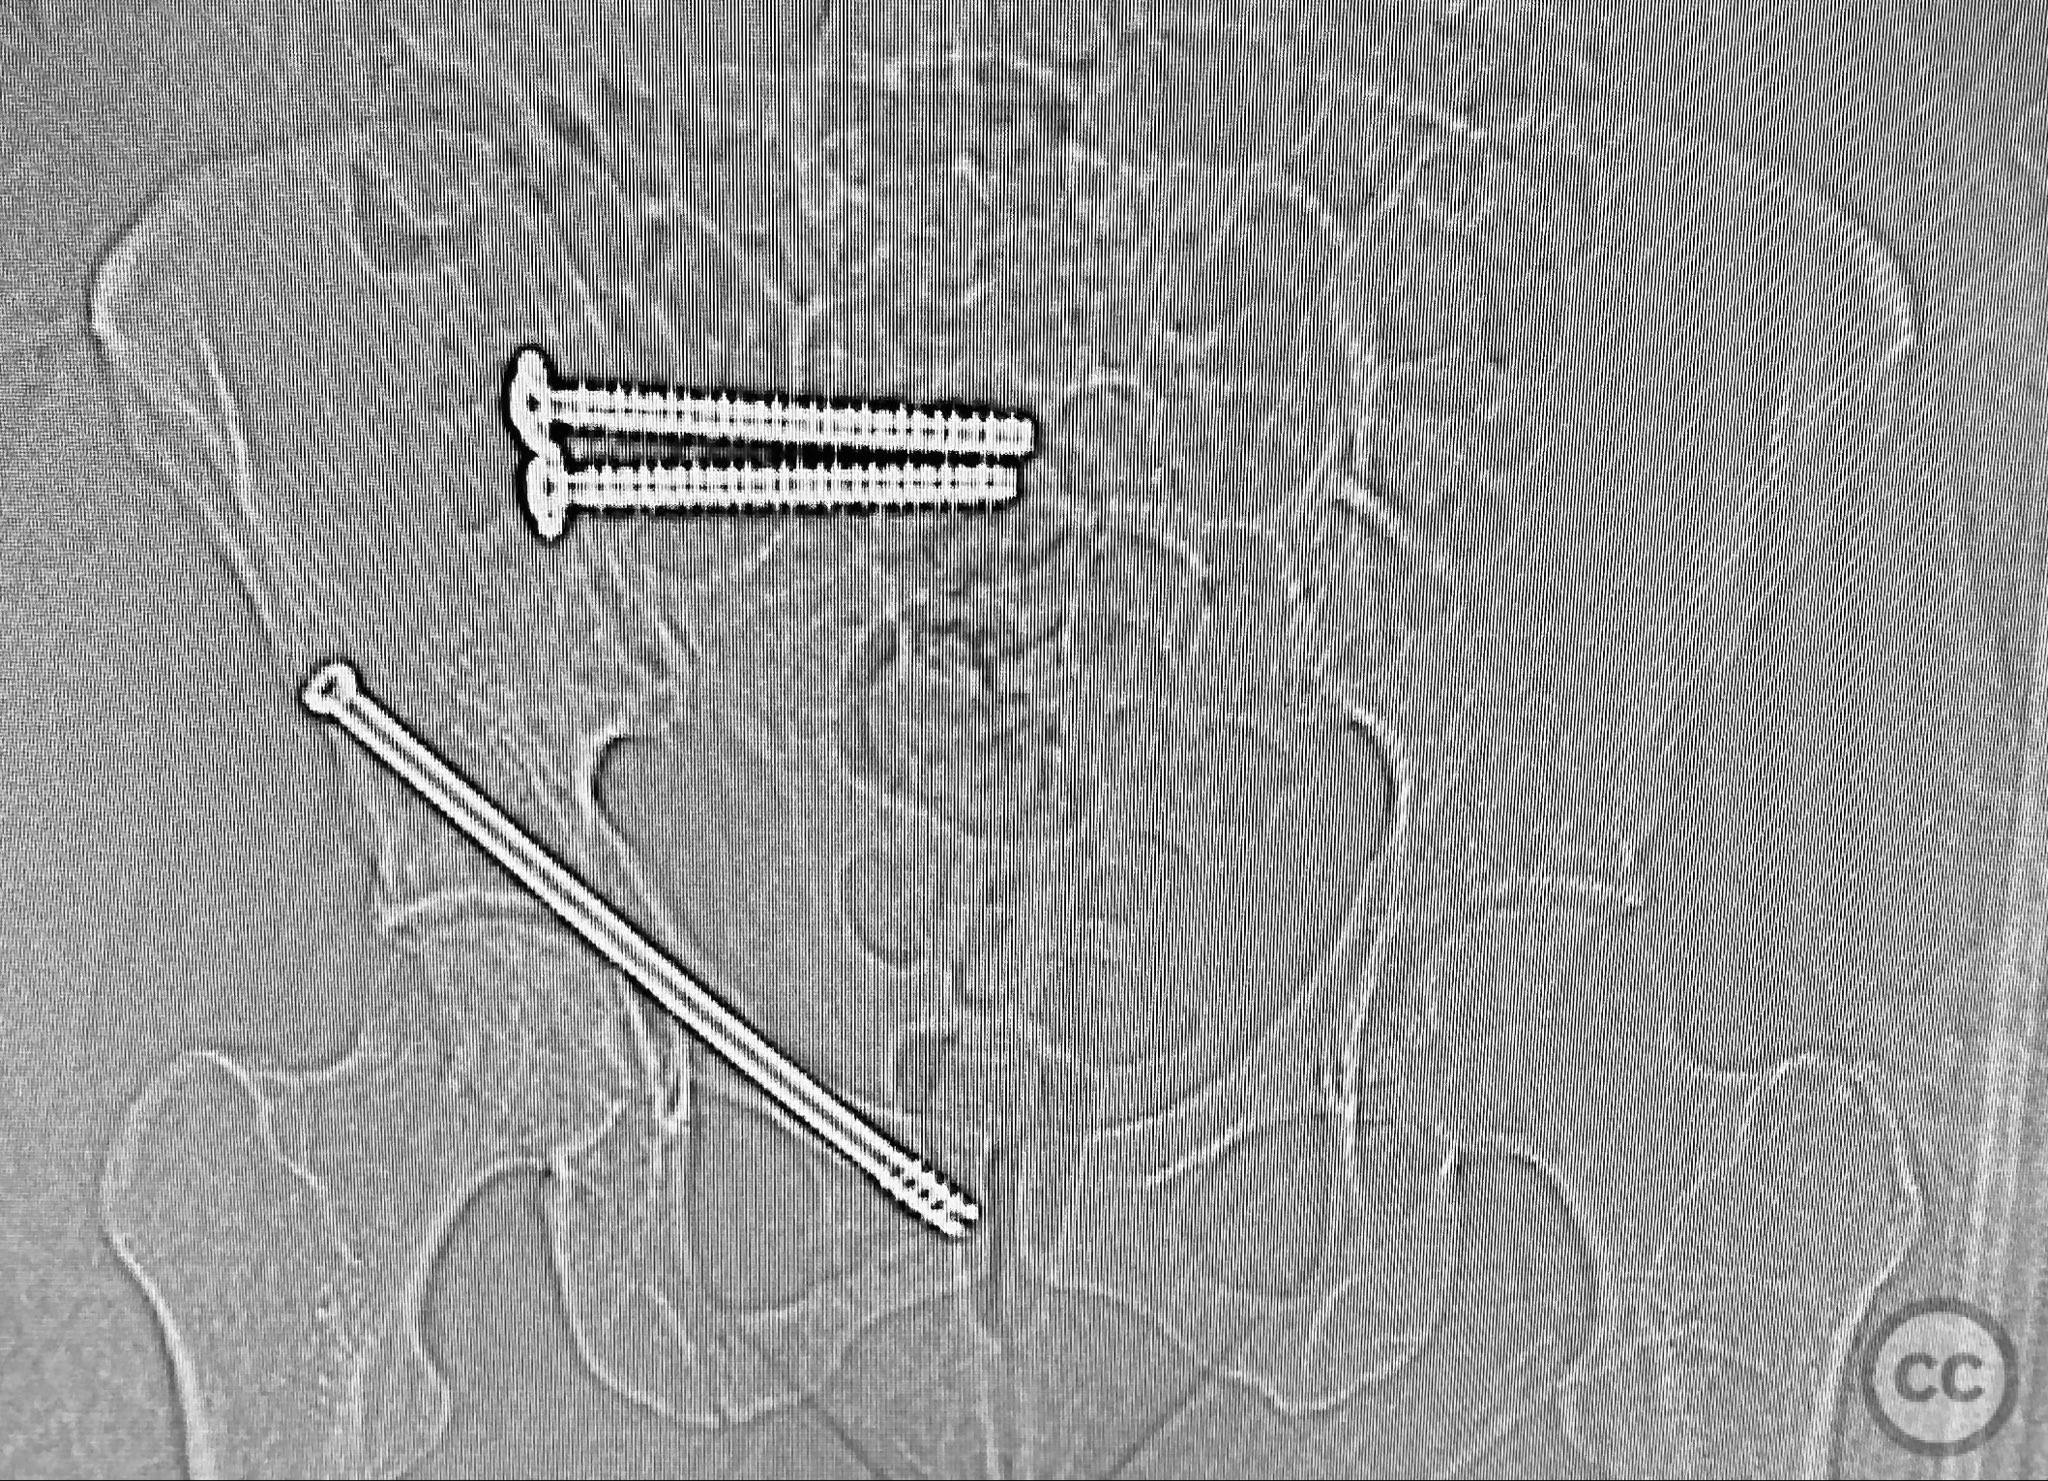

Anatomical surgical approach:  Percutaneous approach: Small stab incisions were made over the crista iliaca and sacral entry points as determined by preoperative imaging. Under fluoroscopic guidance, guidewires were advanced across the sacroiliac joint and sacral ala as indicated. Cannulated screws were inserted percutaneously to stabilize the unstable posterior pelvic ring and rami fractures.

Intraoperative assessment confirmed instability at the posterior pelvic ring with manual stress testing under fluoroscopy. Reduction was achieved with gentle manipulation and maintained during percutaneous screw insertion. The use of intraoperative inlet and outlet views was critical for accurate screw placement and confirmation of reduction. The minimally invasive technique minimized additional soft tissue trauma in this polytrauma patient.

Orthopaedic implants used:   Cannulated percutaneous pelvic screws